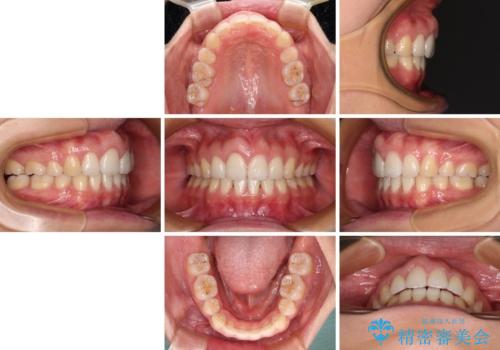

- 前歯の出っ歯と口元の閉じにくさを気にして来院された患者様です。

口元を積極的に引っ込めるために、上下左右の小臼歯4本を抜歯することとしました。

4本の歯を抜歯したことで、飛び出していた口元が引っ込み、横顔が大きく改善されました。

咬み合わせが悪化することのないようにスペースを閉じていくことができ、比較的スムーズに治療を進めることができました。